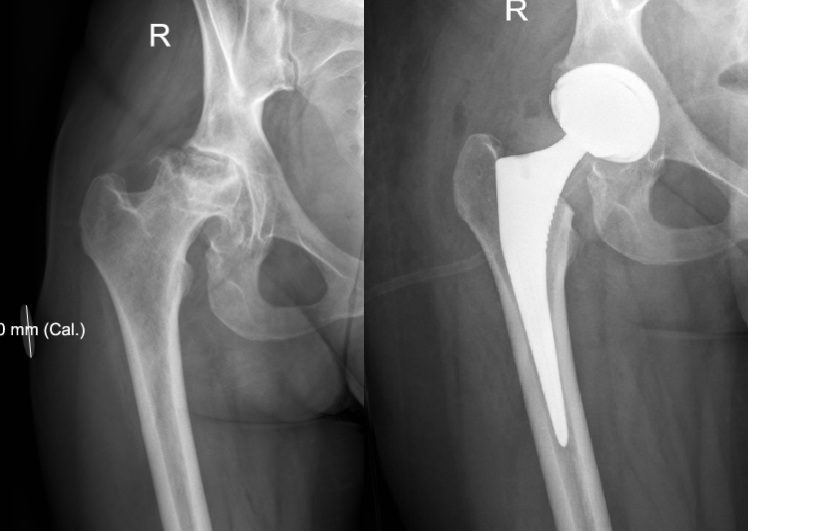

За последние 2-3 года прооперировал пациентов 8 молодого возраста с

АНГБК из "бывших". У 3 точно все хорошо, одна умерла через 2 года после

операции, остальных активно не вызывал, сами тоже не звонят... такой

опыт с ними.

Проблемы с ними бывают, безусловно, один сбежал сразу после синтеза

лодыжек, зимой в тапочках, но и отказать как-то тоже не могу... вот

снимки девушки 27 лет с АНГБК, оперировал на прошлой неделе. Клянется,

что "завязала"... дай Бог! Дочке 2 года...